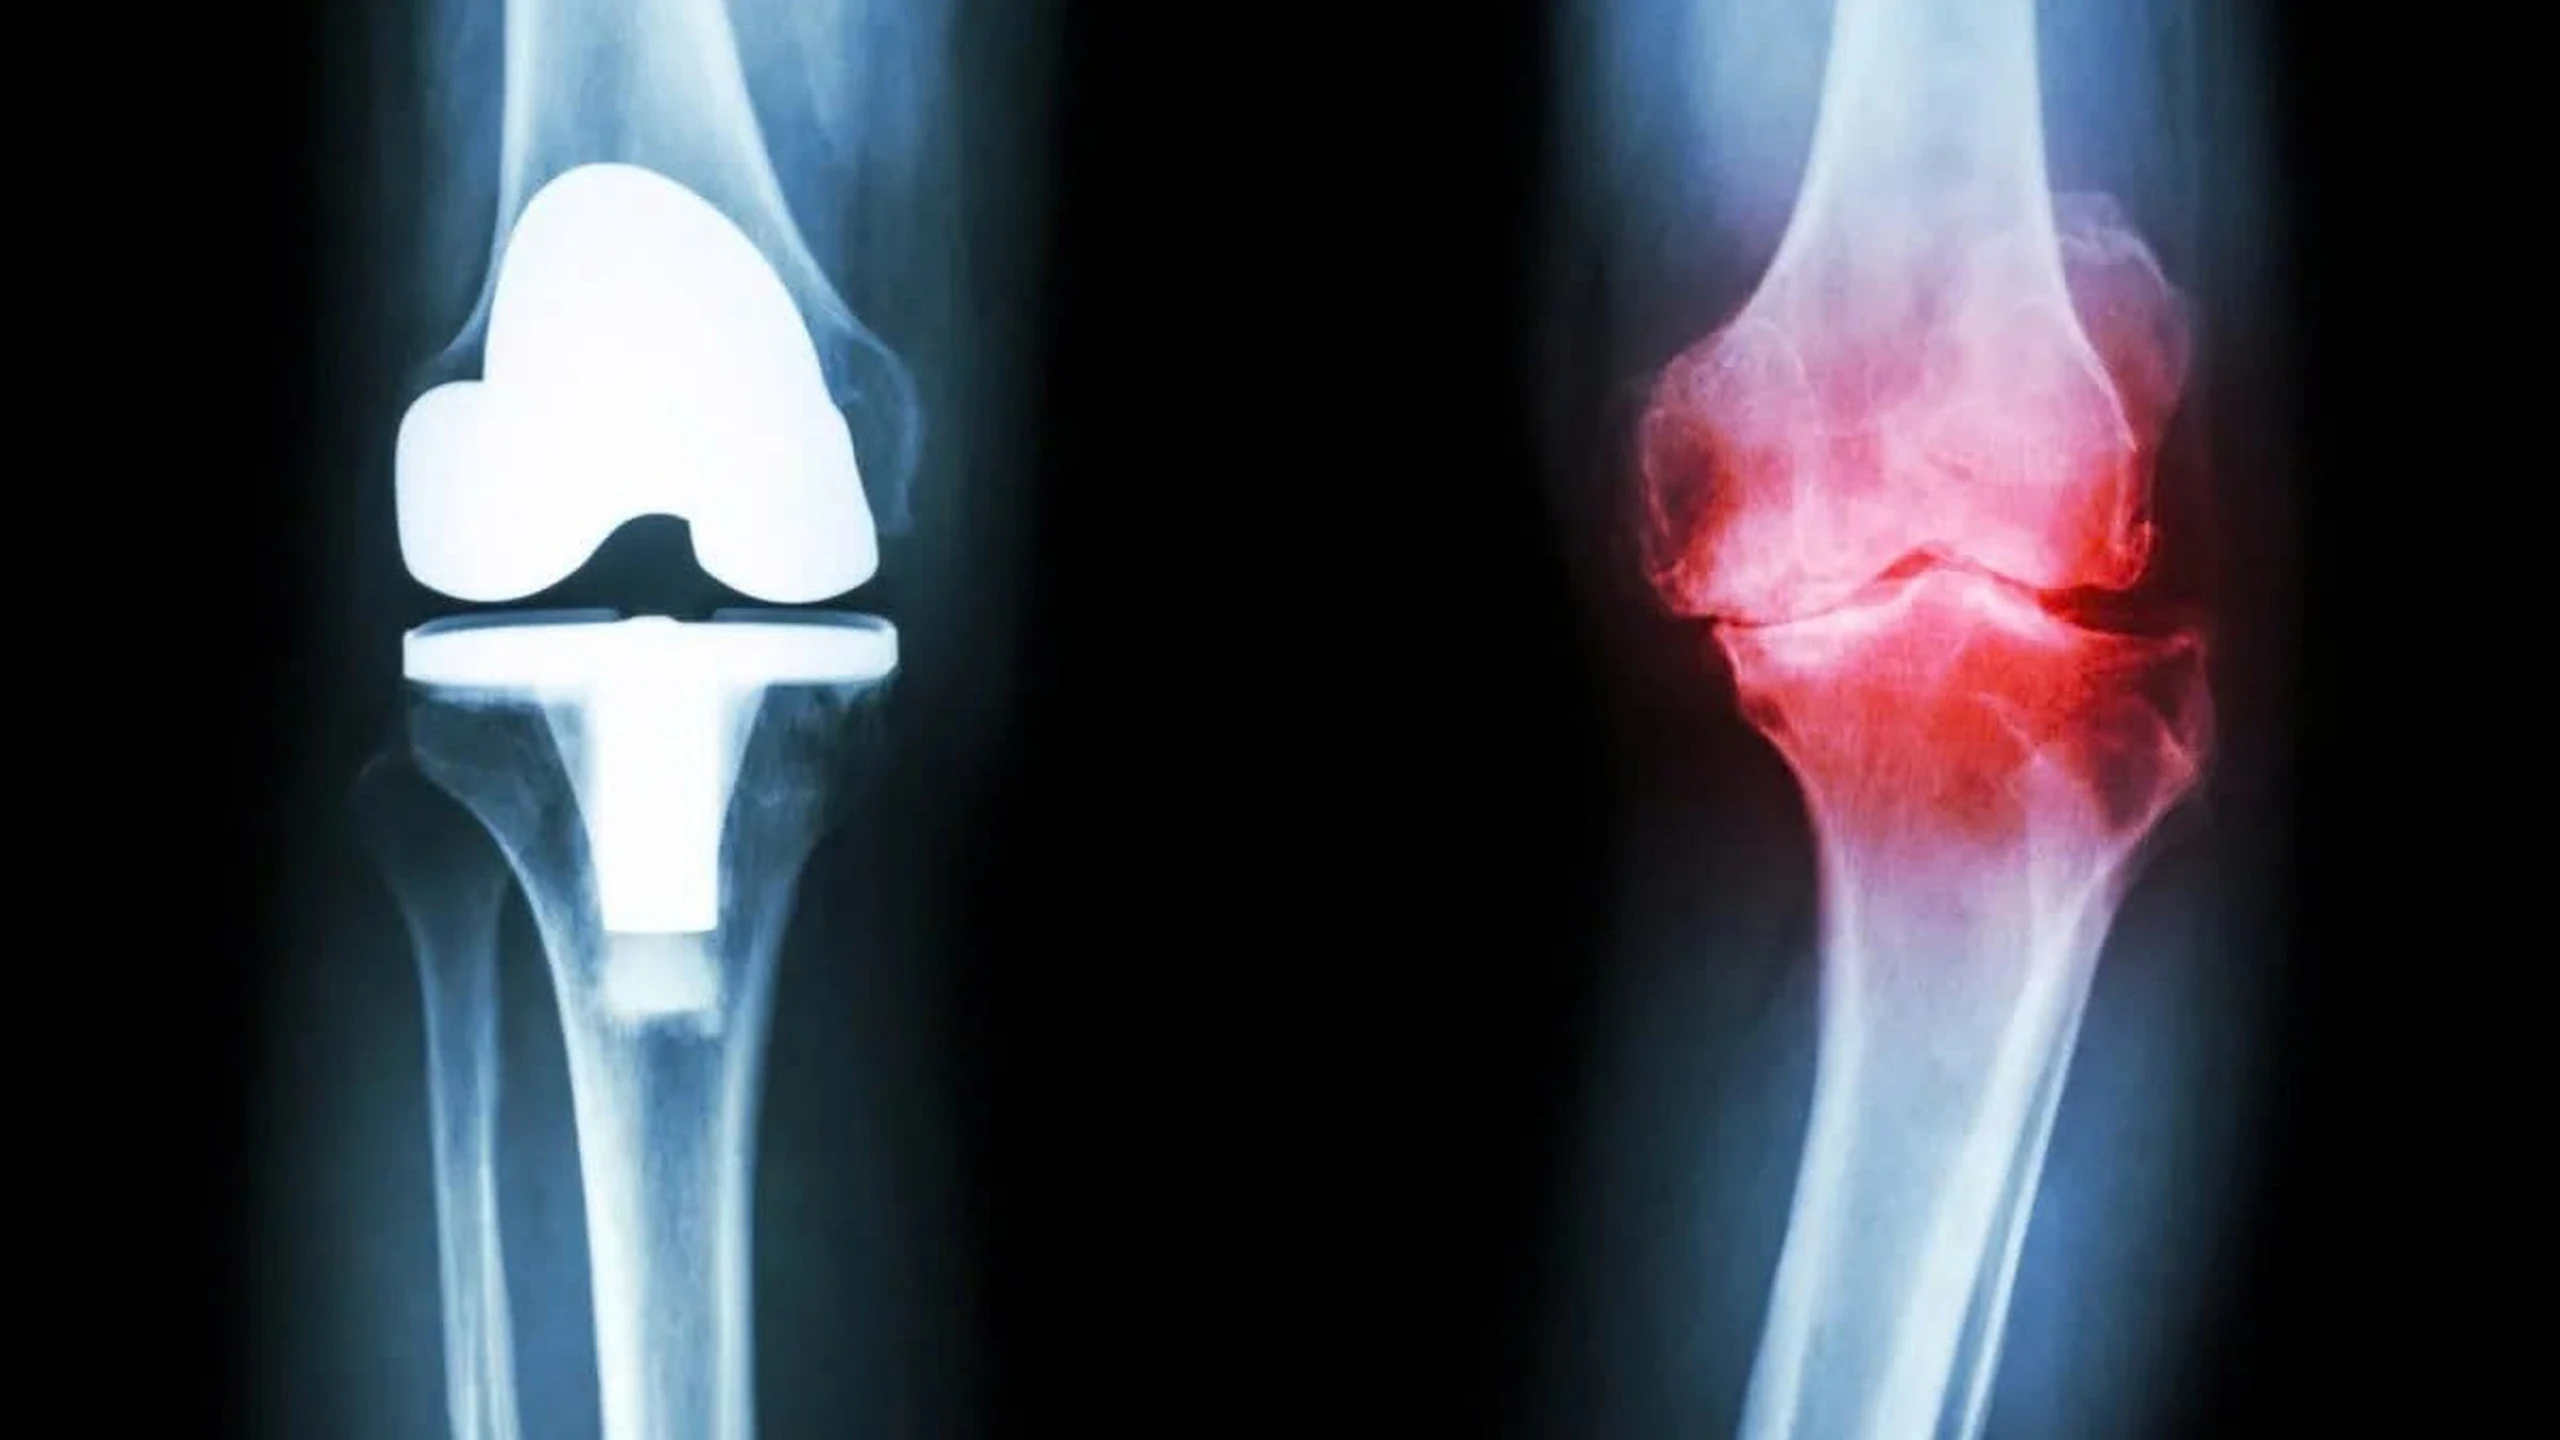

Điều trị phẫu thuật: Được chỉ định khi các phương pháp bảo tồn không còn hiệu quả và chất lượng cuộc sống bị ảnh hưởng nghiêm trọng.

- Đục xương chỉnh trục: Bác sĩ cắt và định dạng lại xương để chuyển trọng lực từ vùng khớp bị hỏng sang vùng lành hơn. Thường dành cho bệnh nhân trẻ (dưới 50 tuổi) và chỉ bị thoái hóa một bên khớp.

- Thay khớp gối bán phần: Chỉ thay thế phần khớp bị hỏng, bảo tồn phần lành lặn. Ưu điểm là hồi phục nhanh và vết mổ nhỏ.

- Thay khớp gối toàn phần: Thay thế toàn bộ bề mặt khớp bằng vật liệu nhân tạo. Đây là giải pháp cuối cùng mang lại hiệu quả giảm đau rõ rệt cho bệnh nhân thoái hóa nặng.